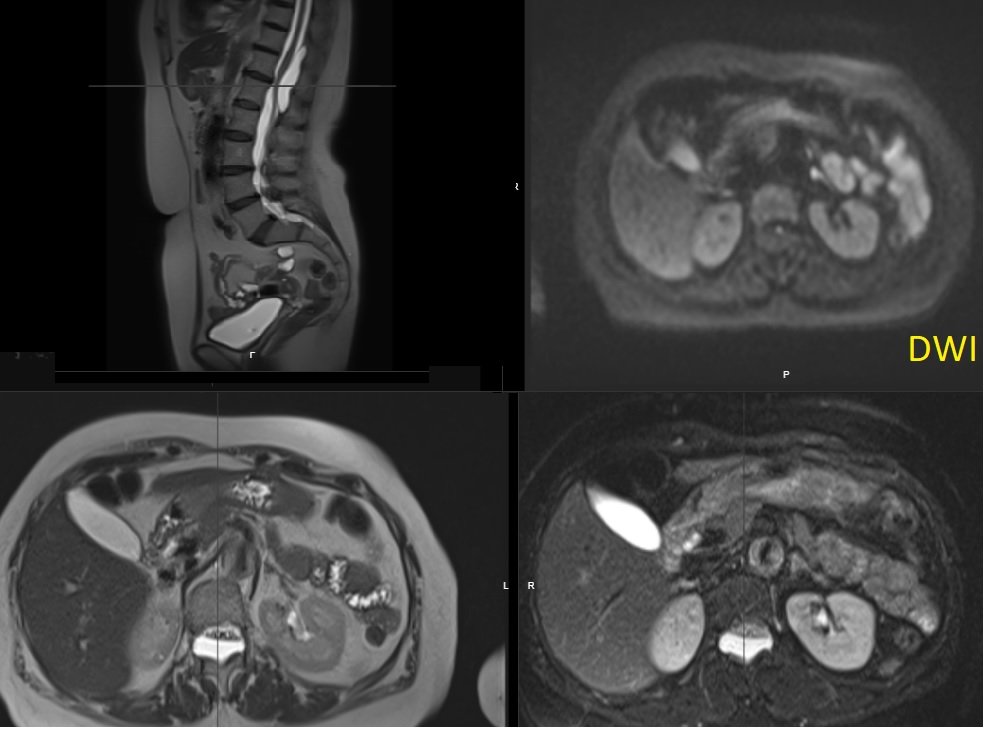

Theme: Spine Back pain in a 30-year-old👨 What are the salient imaging findings? Any further imaging suggested? What further investigations might be useful 💉? #mskrad #spinerad #radtwitter #radres

mskteachingroom's tweet image. Theme: Spine

Back pain in a 30-year-old👨

What are the salient imaging findings? Any further imaging suggested?  What further investigations might be useful 💉?

#mskrad #spinerad #radtwitter #radres